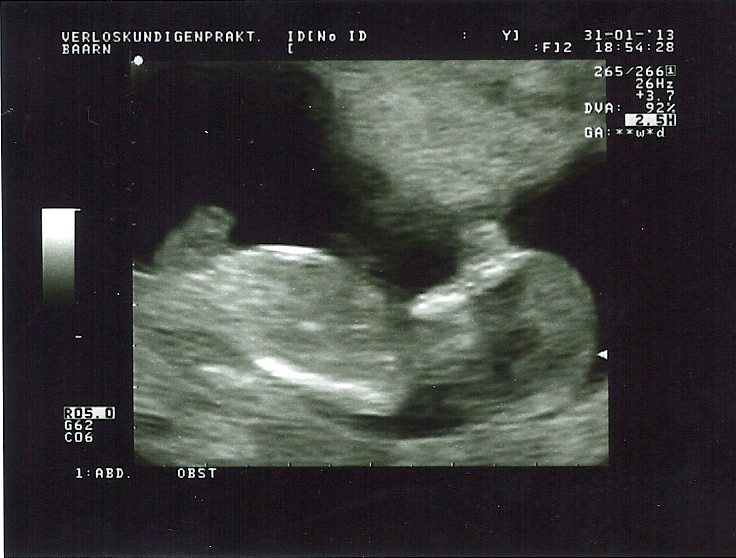

I am not sure if I see a nub in one of these pictures. Maybe the first and last? Any ideas? My mw is leaning towards girl, but on screen it looked a lot clearer than on these photo's... This was this evening, exactly 12w. Thank you for taking a look!

Attachment 8544